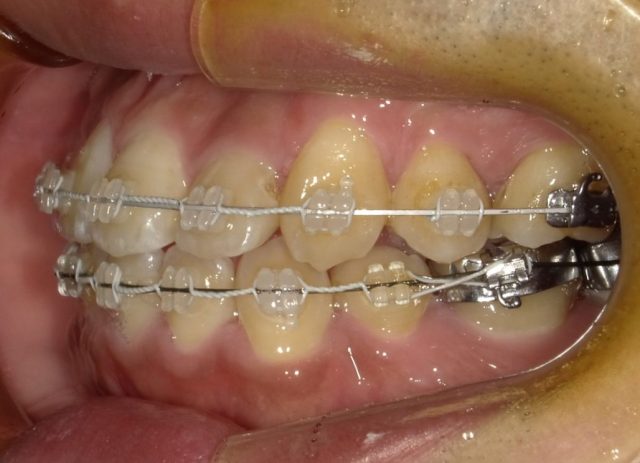

【右側面観】

【左側面観】